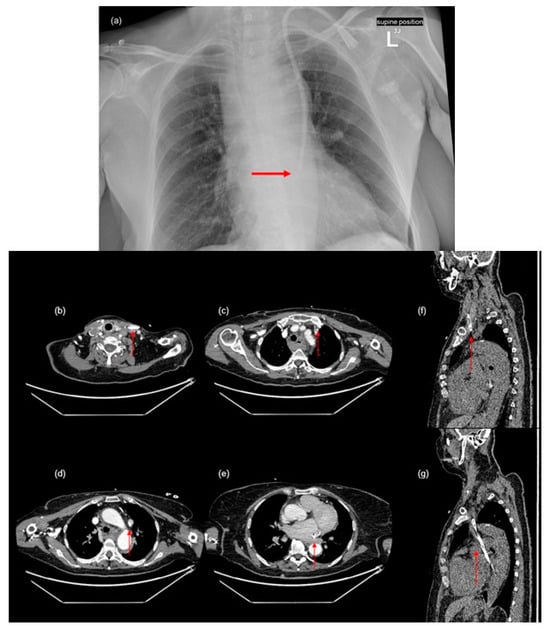

A small pericardial effusion was detected (Figure 2a). Additionally, the imaging shows a hematoma in the posterior mediastinum and common jugular vein thrombosis (Figure 2b,c), which are likely complications of the CVC insertion. The size of the hematoma, which was visible from the foramen magnum to the hiatus of the diaphragm, measured at 53 × 28 × 165 mm. Conservative therapy of the mediastinal hematoma was implemented and was effective in this case.

Due to anemia, the patient received two units of red blood cells. Consultations with a cardiologist, cardiac surgeon, and invasive cardiologist led to the recommendation to remove the dialysis catheter inserted in the left jugular vein. Therefore, the permanent hemodialysis catheter was removed, and a temporary CVC was implanted into the left femoral vein. Dialysis was performed on the temporary catheter without complications. Follow-up imaging showed visible regression of the hematoma and no fluid accumulation in the pericardial sac. Additionally, stenosis of the superior mesenteric artery around the head of the pancreas was discovered (Figure 2d).

Figure 2. Complications following central venous catheter insertion and additional findings observed in this patient ((a)—pericardial effusion (arrow), (b)—mediastinal hematoma (arrow), (c)—common jugular vein thrombosis (arrow), (d)—stenosis of the superior mesenteric artery (arrow)).